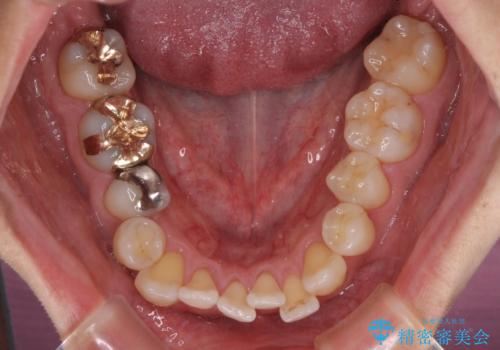

前歯のクロスバイト 目立たないワイヤー装置で矯正治療

- 前歯のクロスバイトを改善したいとのことで来院された患者様です。

舌の突出癖が認められたため、デコボコ改善に伴い前歯が前突する可能性があったため、舌のトレーニングをしっかりと行うよう指導しながら治療を進めることとしました。

舌の突出癖の影響か、下顎前歯がなかなか整わず、治療期間は予定よりも長期間となりました。